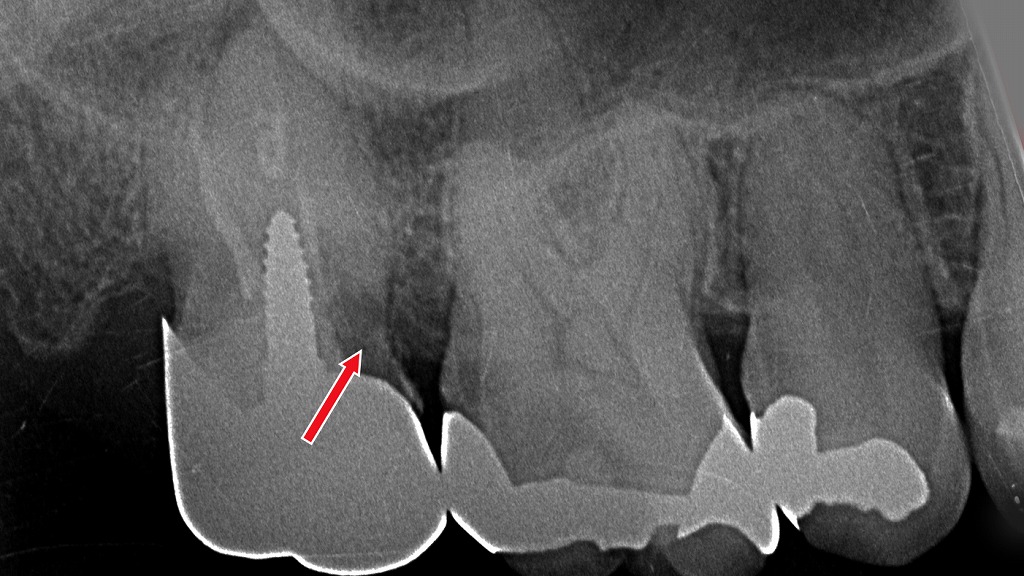

■ 2枚目:埋入直後のパノラマレントゲン

2枚目の画像は、インプラントを埋入した直後のレントゲン写真です。

画像のポイント

- 赤い矢印の先が埋入されたインプラント

- 顎の骨の中に適切な深さ・角度で固定されている

- 神経や隣接歯から安全な距離を確保していることが確認できる

なぜレントゲンが必要なのか

インプラント手術では、

- 神経の位置

- 骨の厚み

- 骨密度

- 上顎洞との距離

などを正確に把握し、安全性を確保する必要があります。

そのため、CT撮影・シミュレーション・サージカルガイドなど

高度な設備や技術を駆使することが重要です。

これらは保険診療の枠組みでは提供できないため、

インプラント治療は自費診療として行われています。